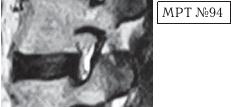

Иллюстрация к книге — Остеохондроз для профессионального пациента [i_115.jpg]

На МРТ № 95 и МРТ № 96 наблюдается практически идентичная картина дегенеративно-дистрофического процесса в поясничном отделе позвоночника у двух разных людей. Исправление физиологического лордоза, значительное снижение высоты межпозвонкового диска в сегменте LV—SI. За счёт сглаживания лордоза суставные поверхности дугоотростчатых суставов, подобно створкам раковины моллюска, раскрываются, суставная капсула растягивается, работа сустава извращается.

В данных случаях в сегментах LV—SI отмечается значительное снижение высоты межпозвонковых дисков, что приводит к образованию подвывиха в дугоотростчатых суставах, который сопровождается смещением верхних суставных отростков нижележащих позвонков кверху и несколько кпереди, стремлением упереться в дужку вышерасположенного позвонка. В нижнем сегменте (МРТ № 96) отчётливо видно, что вследствие подвывиха и смещения суставов образуется не только стеноз межпозвонкового отверстия, но (что важно) происходит и перерастяжение суставной капсулы. В такой ситуации даже сигналы рецепторов дугоотростчатых суставов уже не в состоянии «погасить» возникшую боль.